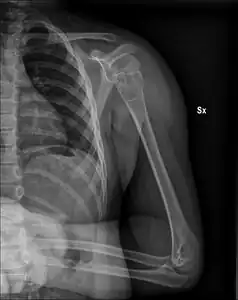

| X-ray: Simple bone cyst in left upper arm of 13 year old | |